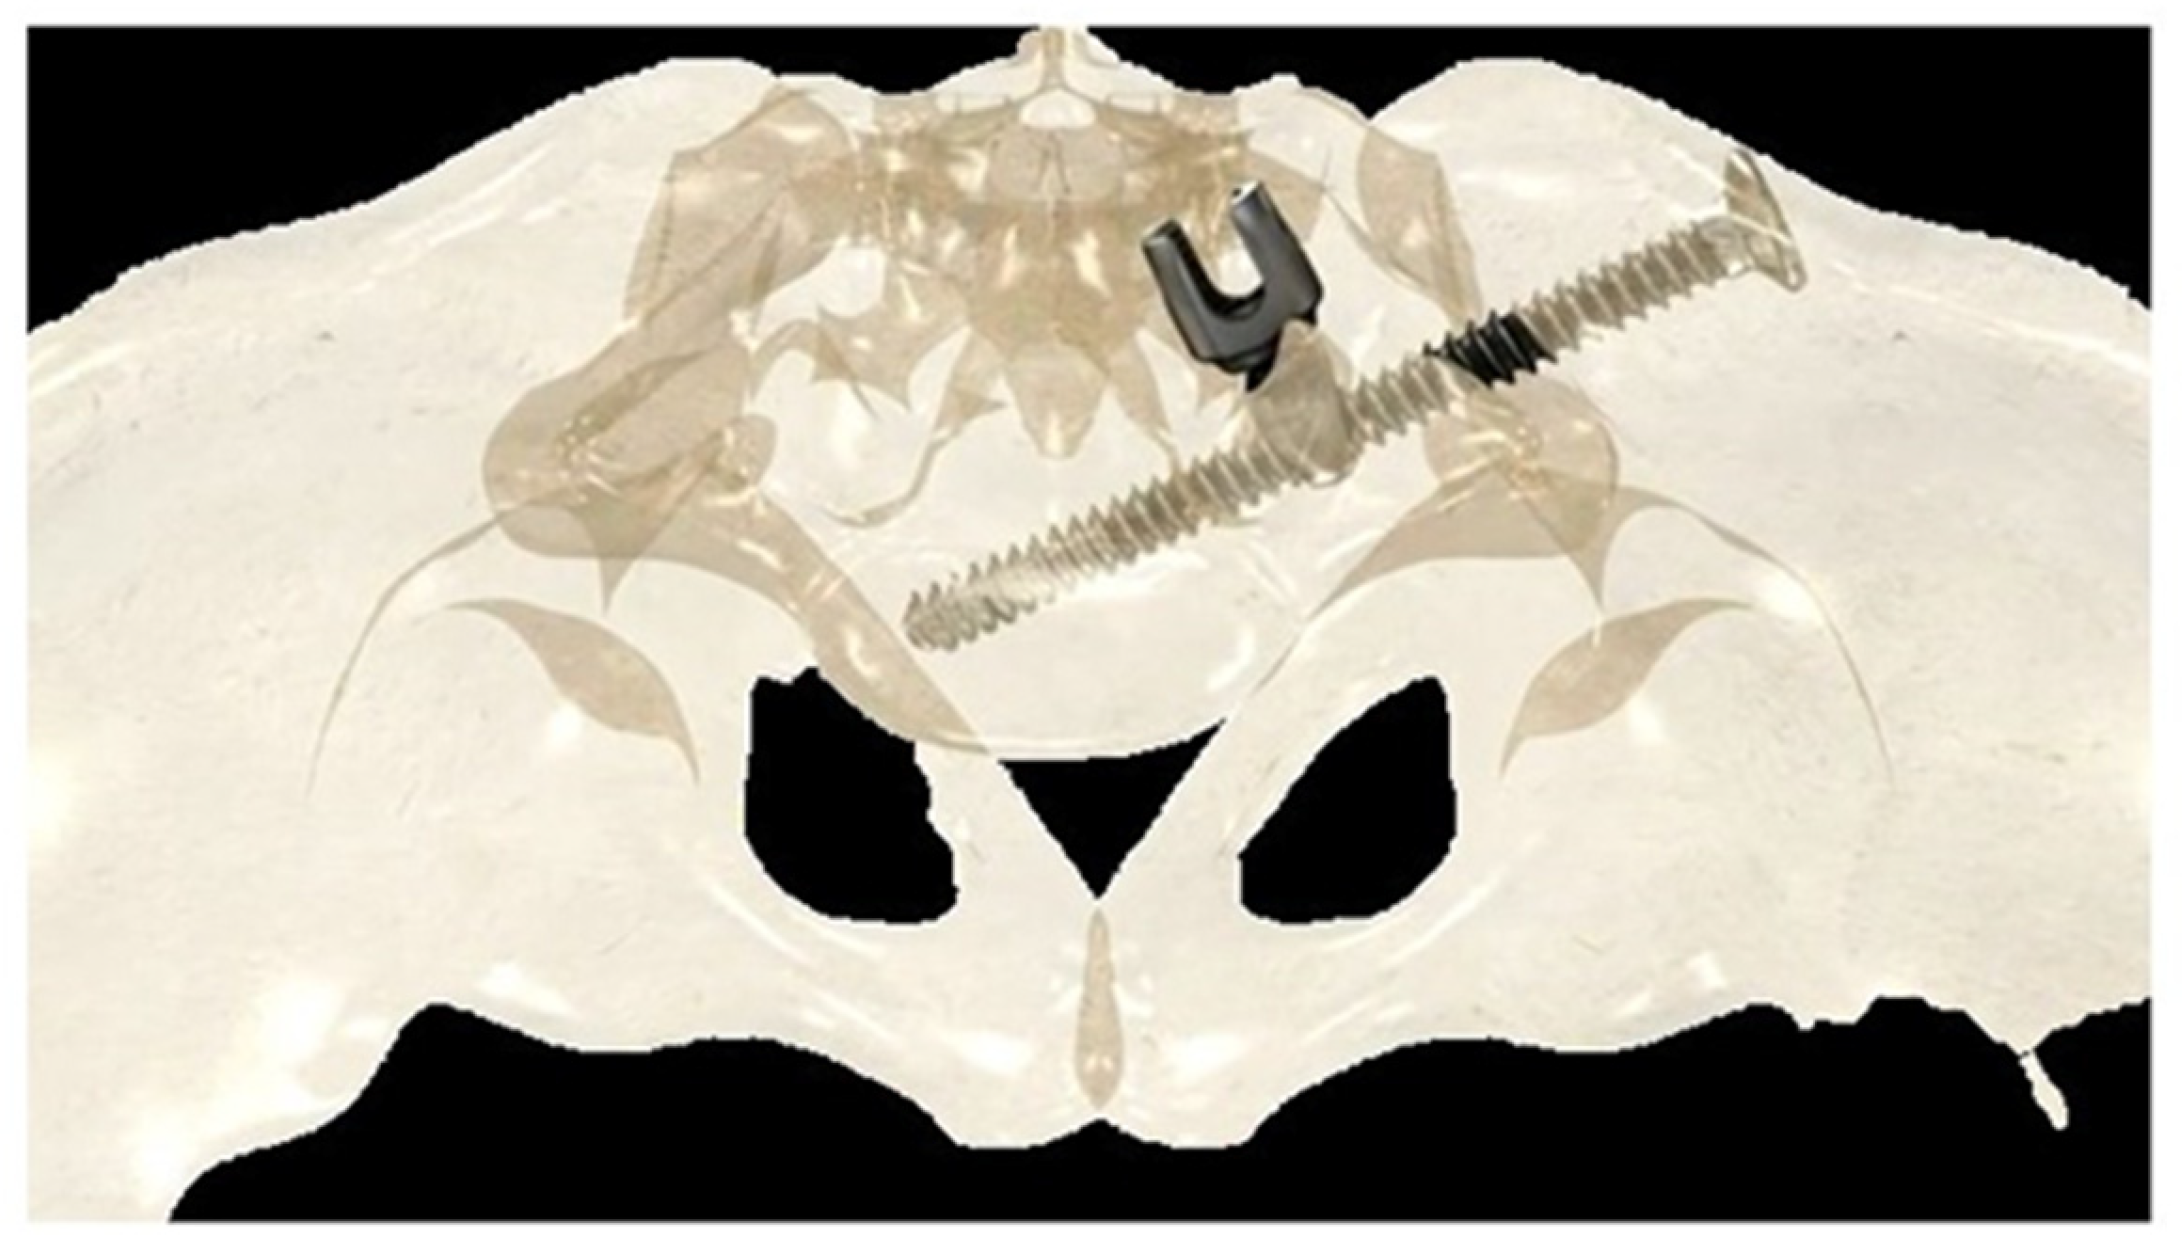

If the construct included the pelvis, an initial short midline incision was made at the lumbosacral junction. A Wiltse intramuscular paramedian approach was used to expose the lumbosacral joint and posterior cortex of the sacrum on each side. A small hole was then created in the sacral cortex, lateral to the articular process of S1, and above the first posterior sacral foramen. An iliosacral connector is inserted into the sacral hole. This connector has a deep ring, into which an iliosacral screw is introduced percutaneously using a bespoke jig, following an oblique posteroanterior direction that avoids the spinal canal, starting from the iliac crest and ending in the body of S1 (Figure 2). The open and polyaxial iliosacral connector allows an easy and secure connection of the rod to the iliosacral screw. The connector has a low profile and is located in a deep position, allowing its use in very young and skinny patients with a body weight of less than 15 kg.

The deep intraosseous direction of the iliosacral screw provides strong and stable pelvic fixation that can be used in all conditions, especially in neuromuscular patients with very osteoporotic bone [26,27].

Figure 2. Drawing showing the bony path of the iliosacral screws passing through the ring of the iliosacral connectors.